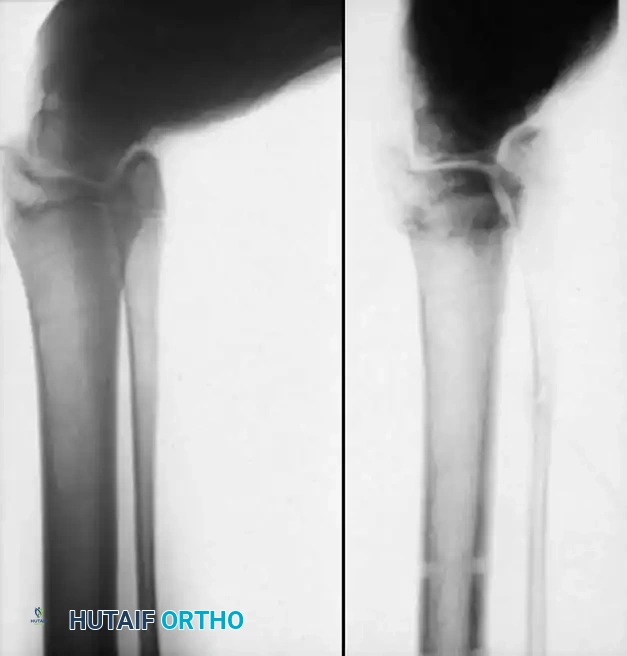

## فهم طبيعة المشكلة وكيفية حدوثها لفهم كيفية حدوث تشوهات القدم في الشلل الدماغي، يجب أن ننظر إلى العلاقة المعقدة بين الأعصاب والعضلات والعظام. في الحالة الطبيعية، تعمل العضلات في أزواج متوازنة (عضلات تشد وأخرى ترخي) لتوجيه حركة المفصل. ولكن في حالة الشلل الدماغي، ترسل الإشارات العصبية غير المنتظمة أوامر مستمرة لبعض العضلات بالانقباض (التشنج)، مما يخلق قوى غير طبيعية وغير متكافئة على عظام ومفاصل القدم. النوع الأكثر شيوعاً من هذه التشوهات هو "القدم الخيلية" أو المشي على أطراف الأصابع، حيث تكون القدم مشدودة لأسفل. وتحدث تشوهات أخرى مثل انحراف القدم للداخل أو انحراف القدم للخارج بنسب متقاربة، وذلك يعتمد بشكل كبير على التوزيع التشريحي للإصابة العصبية لدى الطفل. وقد أثبتت الدراسات الكبرى أن وجود تشوه في القدم، خاصة إذا كان في كلتا القدمين، يؤثر بشكل سلبي وكبير على قدرة الطفل على المشي ويزيد من المجهود البدني المطلوب للحركة مقارنة بالأطفال الذين يعانون من إصابة في قدم واحدة.  ## أسباب وعوامل تطور تشوهات القدم من المهم جداً للآباء أن يدركوا أن تشوهات القدم في الشلل الدماغي نادراً ما تكون ثابتة؛ بل هي تتطور وتتغير ديناميكياً بمرور الوقت، وتحديداً خلال فترات النمو السريع لهيكل الطفل العظمي. تكمن المشكلة الأساسية في أن العظام تنمو بمعدل طبيعي، بينما العضلات المتشنجة والمشدودة (مثل عضلة الساق الخلفية) لا تنمو بنفس السرعة وتفتقر إلى المرونة اللازمة لمواكبة نمو العظام. هذا التفاوت يؤدي إلى قصر نسبي في العضلة والوتر، مما يسحب القدم إلى وضعيات غير طبيعية. على سبيل المثال، قد يبدأ الطفل الصغير بتشوه مرن في القدم، ولكن مع استمرار التشنج العضلي وقوى الشد غير الطبيعية أثناء المشي، قد يتحول هذا التشوه المرن بمرور الوقت إلى تشوه عظمي صلب وتيبس كامل في المفصل. بالإضافة إلى ذلك، فإن تشنج العضلات الدقيقة داخل القدم يمكن أن يؤدي إلى تشوهات ثانوية في الأصابع ومقدمة القدم، مثل انحراف إصبع القدم الأكبر أو التصاق الأصابع. ## الأعراض والعلامات التحذيرية التشوه الأبرز والأكثر شيوعاً هو "القدم الخيلية"، والذي يصيب ما يصل إلى 70% من الأطفال المصابين. وهناك علامات يجب على الآباء الانتباه لها: * المشي المستمر على أطراف الأصابع وعدم القدرة على ملامسة الكعب للأرض. * رجوع الركبة للخلف بشدة أثناء الوقوف أو المشي للتعويض عن قصر وتر أخيل. * صعوبة بالغة في إدخال قدم الطفل في الحذاء العادي. * تآكل الحذاء بشكل غير متساوٍ من جهة معينة. * ألم في القدم أو الساق بعد المشي لمسافات قصيرة. * ظهور تقرحات جلدية في مناطق الضغط غير الطبيعي، خاصة لدى الأطفال الذين يستخدمون الكراسي المتحركة. ## التقييم الطبي والتشخيص يبدأ التقييم الطبي الدقيق بزيارة طبيب جراحة عظام الأطفال المتخصص. سيقوم الطبيب بإجراء فحص سريري شامل لتقييم: * مدى التشنج العضلي في الساق والقدم. * الفرق بين التشوه المرن الذي يمكن تصحيحه باليد، والتشوه الصلب (الثابت). * تحليل نمط مشي الطفل. * إجراء اختبارات خاصة مثل اختبار سيلفرسكيولد لتحديد ما إذا كان الشد ناتجاً عن عضلة الساق العلوية فقط أم يمتد ليشمل وتر أخيل بالكامل. ## الخيارات العلاجية غير الجراحية يعتبر العلاج التحفظي (غير الجراحي) هو خط الدفاع الأول، والهدف الأساسي منه هو الحفاظ على مرونة المفاصل، وتحسين وظيفة القدم، وتأخير الحاجة للتدخل الجراحي قدر الإمكان حتى يكبر الطفل، مما يقلل من احتمالية عودة التشوه. تشمل الخيارات غير الجراحية ما يلي: ### العلاج الطبيعي المكثف يركز العلاج الطبيعي على تمارين الإطالة السلبية للعضلات المتشنجة. وقد أثبتت الأبحاث أن العضلة تحتاج إلى فترات طويلة من الإطالة اليومية لمنع حدوث قصر دائم فيها، وهو ما يتطلب التزاماً كبيراً من الأسرة. ### استخدام الجبائر والأجهزة التعويضية تعتبر الجبائر البلاستيكية الداعمة للكاحل والقدم من أهم أدوات العلاج. وتستخدم الجبائر الليلية الصلبة بشكل خاص للحفاظ على القدم في وضع معتدل ولمواجهة التشنجات التي تزيد أثناء النوم. ### الحقن والجبس المتسلسل يُعد حقن البوتكس في العضلات المتشنجة إجراءً فعالاً لإرخاء العضلة مؤقتاً. وغالباً ما يُتبع الحقن بوضع سلسلة من قوالب الجبس التي يتم تغييرها كل أسبوعين إلى ثلاثة أسابيع لإطالة العضلة تدريجياً وتحسين المدى الحركي للمفصل.  | نوع العلاج التحفظي | الهدف الرئيسي | ملاحظات هامة | | :--- | :--- | :--- | | العلاج الطبيعي | الحفاظ على مرونة العضلات والمفاصل | يحتاج إلى استمرارية والتزام يومي | | الجبائر التقويمية | منع تفاقم التشوه وتثبيت القدم | ضرورية جداً أثناء فترات النوم | | حقن البوتكس | إرخاء العضلات المتشنجة مؤقتاً | تأثيره يستمر لعدة أشهر ويساعد في تأخير الجراحة | | الجبس المتسلسل | إطالة الأوتار تدريجياً | يستخدم غالباً بالتزامن مع حقن البوتكس | ## دواعي التدخل الجراحي لتشوهات القدم يصبح التدخل الجراحي ضرورياً عندما تفشل الطرق التحفظية في السيطرة على التشوه، أو عندما يصبح التشوه ثابتاً ويعيق حياة الطفل. تختلف دواعي الجراحة بناءً على قدرة الطفل على المشي: **للأطفال القادرين على المشي:** يتم اللجوء للجراحة عند عدم قدرة الطفل على وضع كاحله في زاوية قائمة أثناء المشي مع فرد الركبة، مما يؤدي إلى المشي على أطراف الأصابع، أو التواء الركبة للخلف، أو رفع الكعب مبكراً أثناء المشي. **للأطفال غير القادرين على المشي:** تُجرى الجراحة لتخفيف التقلصات الشديدة التي تمنع ارتداء الأحذية، أو تعيق برامج الوقوف المدعوم، أو تتسبب في تقرحات جلدية وصعوبات في النظافة الشخصية. > **تحذير جراحي بالغ الأهمية خطر الإطالة المفرطة** > يجب على الجراح توخي الحذر الشديد لتجنب الإطالة المفرطة لوتر أخيل أو عضلة الساق، خاصة لدى الأطفال الذين يمشون. الإطالة الزائدة تدمر القوة الدافعة للقدم وتؤدي إلى تطور ما يُعرف بـ "مشي القرفصاء". هذا النمط من المشي كارثي من الناحية الميكانيكية، حيث يؤدي إلى إرهاق سريع لعضلات الفخذ الأمامية وفقدان القدرة على المشي المستقل.  ## عمليات تطويل وتر أخيل نظراً لاختلاف حالات الشلل الدماغي، توجد تقنيات جراحية متعددة لتصحيح تشوه القدم الخيلية. تعتمد نسبة نجاح العملية وعدم عودة التشوه بشكل كبير على عمر الطفل وقت الجراحة ونوع الشلل الدماغي. تشير الدراسات إلى أن إجراء الجراحة بعد سن السادسة يقلل بشكل كبير من احتمالية عودة التشوه مقارنة بإجرائها في سن مبكرة جداً. يمكن إطالة مجمع عضلة الساق ووتر أخيل في مستويين رئيسيين: إما عند اتصال العضلة بالوتر، أو في وتر أخيل نفسه. ### التطويل المفتوح لوتر أخيل تُستخدم هذه التقنية (وتعرف بتعديل وايت) وتعتمد على الانزلاق الطبيعي لألياف وتر أخيل التي تلتف حول نفسها بطبيعتها التشريحية.  **خطوات العملية الجراحية:** * يتم عمل شق جراحي طولي خلف الكاحل للوصول إلى الوتر. * يقوم الجراح بعمل قطع جزئي في الجزء السفلي من الوتر، وقطع جزئي آخر في الجزء العلوي في اتجاه معاكس. * عندما يتم دفع القدم بلطف إلى الأعلى (نحو الساق)، تنزلق ألياف الوتر المقطوعة فوق بعضها البعض، مما يؤدي إلى زيادة طول الوتر للمستوى المطلوب لتصحيح التشوه. * تتميز هذه الطريقة بالحفاظ على الغلاف المحيط بالوتر لمنع الالتصاقات.   بعد العملية، يتم وضع قدم الطفل في جبس قصير يمتد تحت الركبة لمدة 4 أسابيع، ويُسمح للطفل بالمشي عليه. بعد إزالة الجبس، يتم استخدام جبيرة بلاستيكية مخصصة للحفاظ على النتيجة. ### التطويل على شكل حرف زد توفر هذه التقنية تحكماً دقيقاً للغاية في مقدار الإطالة المطلوبة، مما يجعلها الخيار الأمثل للتقلصات الشديدة والصلبة.  **كيف تتم العملية؟** * يتم شق الوتر طولياً في المنتصف، ثم يتم قطع نصف الوتر من الأسفل والنصف الآخر من الأعلى، مما يشكل حرف Z. * يتم سحب الأطراف لزيادة الطول بدقة متناهية، ثم يتم خياطة الأطراف معاً باستخدام خيوط جراحية قوية. * يتم ضبط درجة شد الوتر بناءً على شدة التشنج العضلي لدى الطفل لضمان أفضل نتيجة وظيفية.      يتطلب هذا الإجراء وضع جبس لمدة 6 أسابيع، يليه استخدام الجبائر الداعمة بشكل مستمر لتجنب سقوط القدم. ### التطويل عن طريق الجلد تعتبر هذه التقنية إجراءً سريعاً وبسيطاً يتم إجراؤه غالباً كجراحة يوم واحد، وتتميز بآثار ندبات شبه معدومة ونتائج ممتازة.  **تفاصيل الإجراء:** * يقوم الجراح بعمل ثلاثة شقوق صغيرة جداً (ثقوب) في الجلد فوق وتر أخيل باستخدام شفرة دقيقة. * يتم قطع نصف الوتر من خلال هذه الثقوب في مستويات مختلفة (أسفل، وسط، أعلى). * عند دفع القدم للأعلى، تنزلق الألياف وتستطيل العضلة، وغالباً ما يُسمع صوت "طقطقة" بسيطة تدل على تحرر الوتر ووصوله للطول المطلوب. * لا يتطلب هذا الإجراء خياطة جراحية، بل يتم وضع أشرطة لاصقة معقمة ثم الجبس.   ## عمليات إطالة عضلة الساق الخلفية عندما يظهر الفحص الطبي أن المشكلة تكمن فقط في الجزء العلوي من عضلة الساق (عضلة السمانة)، أو عندما يريد الجراح تقليل خطر الإطالة المفرطة لدى طفل قادر على المشي، يتم اللجوء إلى إطالة الغشاء العضلي لعضلة الساق بدلاً من قطع وتر أخيل السفلي. هناك عدة طرق جراحية تاريخية وحديثة لهذا الإجراء (مثل تقنية ستراير، فولبيوس، وبيكر)، وتعتمد جميعها على فصل الغشاء الليفي للعضلة في منطقة اتصالها بالوتر، مما يسمح للعضلة بالتمدد والاستطالة مع الحفاظ على قوة الدفع الأساسية للقدم.   أثبتت الدراسات أن هذه التقنية تعطي نتائج ممتازة ونسبة عودة للتشوه لا تتجاوز 4% عند اختيار المريض المناسب. > **معلومة طبية هامة** > في الماضي، كان بعض الجراحين يقومون بقطع جزء من الأعصاب المغذية للعضلة لتقليل التشنج. هذا الإجراء لم يعد مستخدماً في الطب الحديث، حيث يتم السيطرة على التشنج الآن بطرق أفضل مثل حقن البوتكس أو عمليات إطالة الأوتار.   بعد هذه الجراحة، يتم وضع جبس لمدة 4 أسابيع، ويُنصح بشدة بالبدء في العلاج الطبيعي المكثف بعد فك الجبس للحفاظ على مرونة المفصل، مع استخدام الجبائر الليلية لمدة لا تقل عن 6 أشهر.   ## علاج اعوجاج القدم للداخل أو الخارج بينما يعتبر المشي على أطراف الأصابع هو التشوه الأكثر شيوعاً، فإنه غالباً ما يكون مصحوباً بانحراف القدم للداخل أو الخارج. اتجاه الانحراف يعتمد على نوع الشلل الدماغي وقوة العضلات المتشنجة التي تسحب القدم في اتجاهها. في حالات الشلل النصفي، غالباً ما تنحرف القدم للداخل. أما في حالات الشلل المزدوج أو الرباعي، فغالباً ما تنحرف القدم للخارج وتصبح مسطحة. **المبادئ الجراحية لتصحيح الاعوجاج:** انحراف القدم للداخل يعتبر أكثر إعاقة للطفل لأنه يجعله يمشي على الحافة الخارجية للقدم، مما يسبب عدم استقرار وصعوبة في استخدام الجبائر. لذلك يتم التدخل الجراحي مبكراً. يتطلب تصحيح هذه التشوهات التعامل مع شقين: 1. **التشوه الديناميكي العضلي:** يتم علاجه عن طريق نقل الأوتار (مثل نقل نصف وتر العضلة الأمامية للساق) لإعادة التوازن لقوى الشد في القدم. 2. **التشوه العظمي الثابت:** إذا كان التشوه قد أثر على شكل العظام، يتطلب الأمر تدخلاً في العظام نفسها، مثل إجراء قص عظمي في عظمة الكعب لتعديل مسارها وإعادة القدم لوضعها المسطح الطبيعي الذي يسمح بارتداء الأحذية والجبائر.    ## مرحلة التعافي وما بعد الجراحة تعتبر فترة ما بعد الجراحة بنفس أهمية الجراحة ذاتها لضمان نجاح العلاج. * **الجبس:** يبقى الطفل في الجبس لفترة تتراوح بين 4 إلى 6 أسابيع حسب نوع الإجراء. * **المشي:** في كثير من الحالات، يُسمح للطفل بالمشي على الجبس بمجرد زوال الألم الأولي (عادة بعد 5 إلى 10 أيام). * **الجبائر:** بعد إزالة الجبس، يكون استخدام الجبائر البلاستيكية (AFO) إلزامياً، إما طوال اليوم أو أثناء الليل فقط، وذلك حسب حالة الطفل وقوة عضلاته. * **العلاج الطبيعي:** يبدأ برنامج مكثف للعلاج الطبيعي لتقوية العضلات الضعيفة وتدريب الطفل على نمط المشي الجديد والصحيح. ## الأسئلة الشائعة حول تشوهات القدم في الشلل الدماغي ### متى يجب التدخل الجراحي لعلاج تشوهات القدم؟ يُنصح بالتدخل الجراحي عندما تفشل العلاجات التحفظية (مثل الجبائر والعلاج الطبيعي) في تحسين المشي، أو عندما يصبح التشوه ثابتاً ويسبب ألماً أو يمنع الطفل من ارتداء الأحذية والمشي بشكل متوازن. ### هل يمكن أن تعود التشوهات بعد إجراء العملية الجراحية؟ نعم، هناك احتمالية لعودة التشوه، وتعتمد النسبة على عمر الطفل وقت الجراحة وشدة التشنج. إجراء الجراحة بعد سن السادسة يقلل بشكل كبير من احتمالية الانتكاس، بالإضافة إلى الالتزام بارتداء الجبائر بعد العملية. ### ما هي مدة بقاء الجبس بعد عملية تطويل الأوتار؟ عادة ما يستمر وضع الجبس لمدة تتراوح بين 4 إلى 6 أسابيع، وذلك يعتمد على نوع التقنية الجراحية المستخدمة وما إذا كانت هناك إجراءات إضافية على العظام. ### هل يمكن علاج المشي على أطراف الأصابع بدون جراحة؟ في المراحل المبكرة وعندما يكون التشوه مرناً، يمكن السيطرة عليه باستخدام العلاج الطبيعي المكثف، الجبائر الليلية، وحقن البوتكس. ولكن إذا أصبح الوتر قصيراً بشكل دائم، تصبح الجراحة ضرورية. ### ما هو مشي القرفصاء ولماذا يحذر منه الأطباء؟ مشي القرفصاء يحدث عندما يتم إطالة وتر أخيل بشكل مبالغ فيه أثناء الجراحة، مما يفقد القدم قوة الدفع، فيضطر الطفل لثني ركبتيه بشكل مستمر أثناء المشي. هذا النمط مرهق جداً وقد يفقد الطفل القدرة على المشي المستقل. ### هل حقن البوتكس تغني عن العملية الجراحية؟ البوتكس علاج مؤقت يعمل على إرخاء العضلة المتشنجة لعدة أشهر، ويساعد في تأخير الحاجة للجراحة حتى يصل الطفل لعمر مناسب، لكنه لا يعالج القصر العضلي الثابت ولا يغني عن الجراحة في الحالات المتقدمة. ### متى يستطيع الطفل المشي بعد العملية؟ في معظم عمليات إطالة الأوتار، يُسمح للطفل بالبدء في المشي التدريجي وهو يرتدي الجبس بمج ---